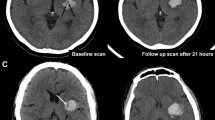

Moderation Effect of ICH Energy

Our findings indicate a significant positive moderation by ICH energy on the reduction of 30-day mortality following surgical treatment (OR: 0.932; 95% CI: 0.884–0.988; p = 0.01) (Table 2). To distinguish between patients with low and high nergye, we established the cut-off point for such moderation at 27.92 (p < 0.01). Examples of ICH with high and low energy are presented in Fig. 2. Among patients above this threshold (54.50%) surgical treatment was independently associated with a lower risk of 30-day mortality (OR: 0.113; 95% CI: 0.015–0.593; p = 0.02). Additionally, a lower GCS score upon admission (OR: 0.731; 95% CI: 0.632–0.83; p < 0.01), a larger volume of ICH (OR: 1.26; 95% CI: 1.021–1.53; p = 0.043), higher glucose levels at admission (OR: 1.246; 95% CI: 1.091–1.476; p < 0.01), and the presence of IVH (OR: 3.177; 95% CI: 1.366–7.769) were independently associated with an increased risk of 30-day mortality. Below determined threshold (45.50%) only older age (OR: 1.068; 95% CI: 1.025–1.120; p < 0.01) and the subtentorial location (OR: 1.020; 95% CI: 1.003–1.041; p = 0.031) were independently associated with higher risk of 30-day mortality (Table 3, Fig. 3).